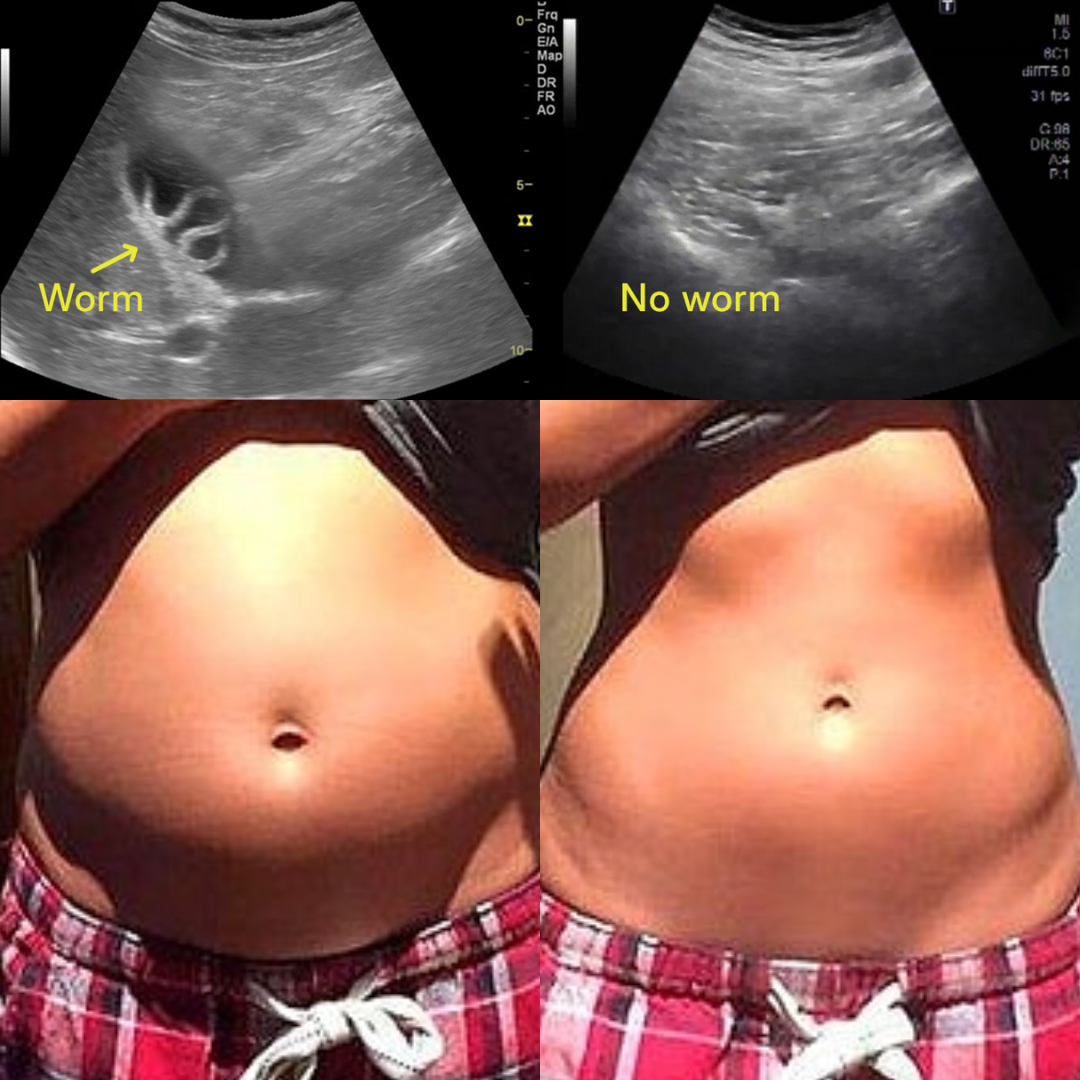

Hidden toxins, parasites, and microplastics are draining your energy and aging you faster than you realize.

Every breath, sip, and bite exposes you to a toxic storm of parasites, metals, plastics, and hidden chemicals. They build up in your body, draining your energy, clouding your mind, and accelerating aging from the inside. This isn't your fault — your body was never built to fight off this many invaders alone.

Eliminate parasites to reduce bloating and unexplained cravings. Bind and flush heavy metals to support liver and brain health. Capture microplastics to help you feel lighter and more energized.